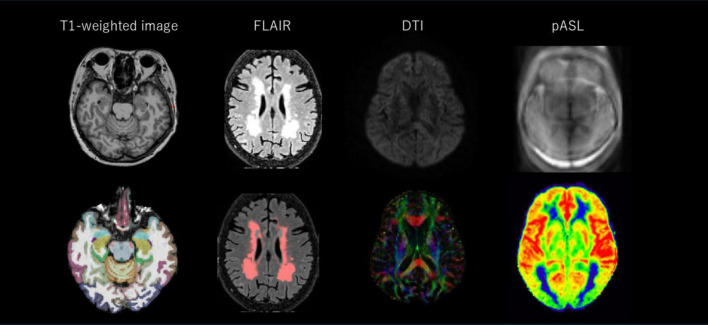

Background: Early detection of mild cognitive impairment (MCI), defined as the prodromal stage of dementia, is key to delaying the progression to dementia through lifestyle interventions and/or pharmacological treatments. This study aimed to develop and test new identification models for MCI in community settings based on multiple sources of clinical features, including neuroimaging biomarkers.

Methods: This cross-sectional study analyzed cognitive testing and MRI examination data from 148 community-dwelling older adults in Nobeoka City. MCI was assessed using the Memory Performance Index from the MCI Screen. The variables used for model development were multisource features, including MRI-derived biomarkers and cognitive test scores. Finally, MCI identification models were developed using a penalized logistic regression model with an elastic net algorithm.

Results: Among the 148 participants (mean age, 78.6 ± 5.2 years), 44.6% were identified as having MCI. The area under the curve for the elastic net model using baseline variables (i.e., age, sex, and education) and the multisource model were 0.74 (95% confidence interval, 0.59 to 0.89) and 0.81 (0.67 to 0.94) in the test datasets, respectively. The addition of neuroimaging biomarkers and cognitive test scores significantly improved the performance of the model identifying MCI (p = 0.012 by DeLong's test). The structural, perfusion, and diffusion MRI-derived biomarkers remained in the identification model with variable selection with the elastic net algorithm, and were thus considered important variables.

Conclusion: Our multisource elastic net model demonstrated high performance at detecting MCI, suggesting that the combination of multimodal neuroimaging biomarkers contributes to MCI discrimination.